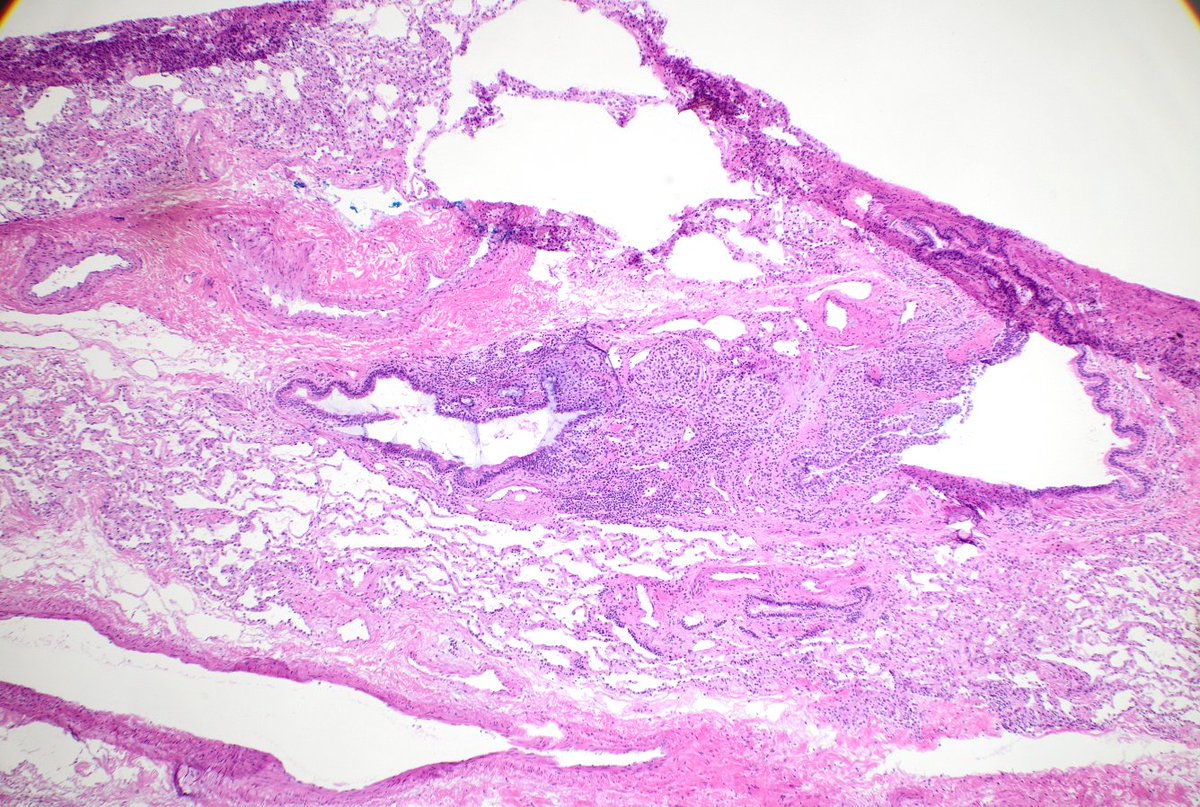

Incidental finding. Resection for met CA + CHF hx. Anything striking in alveolar septae imgs? Consider thoracic path training @MoffittNews "to contribute to the prevention and cure of cancer, focusing on groundbreaking research, expert patient care, and comprehensive education"

Diagnosing granulomatosis with polyangiitis on small biopsies (especially if not considering it) is very challenging. ANCA serologies, negative cultures, and pathologic suspicion were crucial in this case. Not everything is cancer at a cancer center. #lungpath #pathology #moffitt